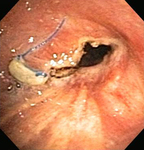

Бронхоскопическая терапия для обструкции нижних дыхательных путей правого главного бронха: постмеханическая циторедукция

Из коллекций Хосе Фернандо Сантакруза, дипломированного врача, члена Американской коллегии специалистов в области торакальной медицины, DAABIP, и Эрика Фолка, дипломированного врача, магистра наук; используется с разрешения